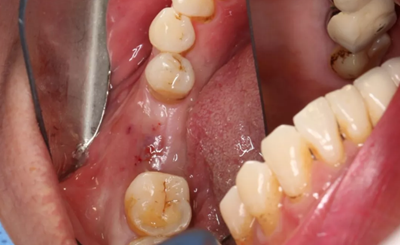

2、術(shù)前口腔內(nèi)照片

46牙烤瓷冠修復(fù),牙周紅腫,叩痛,松2度。骨吸收波及鄰牙,鄰牙牙周情況不佳,45牙松2度,47牙松1度。

(攝于2016年8月31日,反光板協(xié)助拍攝)